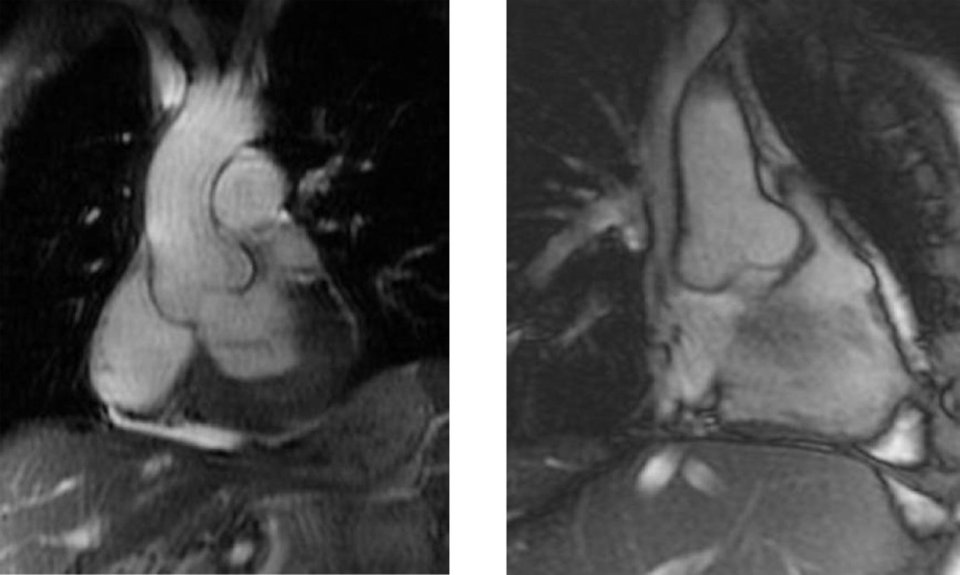

Aortenwurzeldilatation bei einem Patienten mit Morbus Fabry. Aortenwurzeldilatation bei einem Patienten mit Morbus Fabry. © wikimedia/Pr Olivier Dubourg and Pr Dominique Germain, University of Versailles – St Quentin en Yvelines